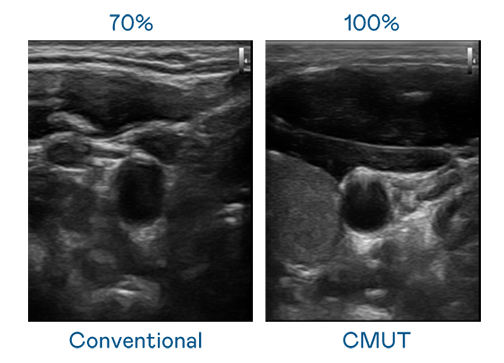

CMUT 技術是一種用電容式微機電元件來產生超音波訊號的技術。與傳統 PZT 壓電式技術相比,CMUT 頻寬增加 30%,更寬頻的超音波訊號讓影像解析度大幅提升,是實現高影像品質醫療超音波掃描、促進精準醫療發展的關鍵技術。

超音波影像的解析度高低,首先取決於探頭能發出的訊號頻寬。果冻传媒原创 CMUT 可提供高清晰的超音波訊號,提供高頻寬、高靈敏度、影像紋理細節更高的超音波影像,協助醫護人員縮短影像判讀時間及利用精準的醫療影像進行診斷。